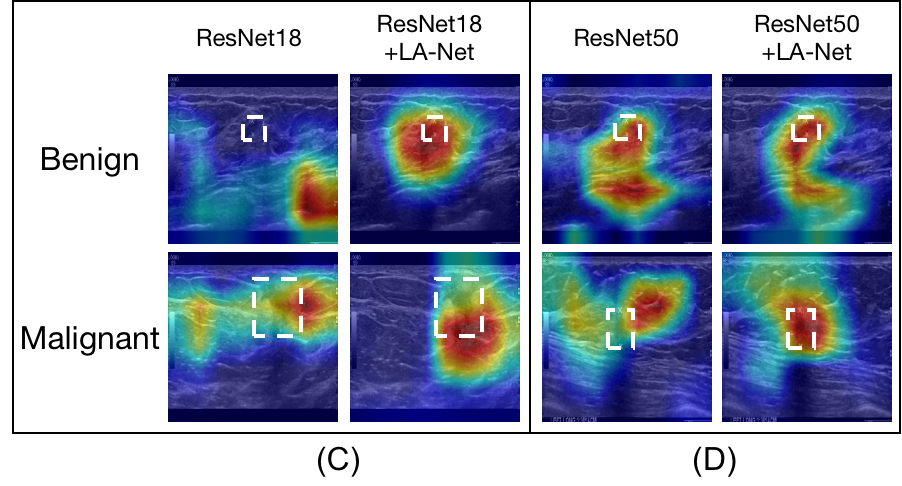

4.5 Classification result interpretation by visualizing the discriminative region

To improve model interpretability, class activation mapping (CAM) [15] was proposed to describe how a DL-based model predicts the outcome by identifying discriminative regions on a given image and employed broadly to interpret classification networks in BUS image analysis field [40, 35]. Particularly, Grad-CAM, an effective generalization of CAM which is applicable for a variety of CNN models, can provide class-discriminative localization for visual explanations [41]. It computes the gradient score for each class in terms of the feature map activation of the last convolutional layer in a CNN model, which renders high-level semantic and spatial information. In this study, Grad-CAM was employed to highlight the potential ROIs based on the extracted feature of the last convolutional layer of FEX, representing the learned spatial information for classification. As shown in Figure 15, the attention regions recognized by our method have higher overlaps with the GT lesion locations. It indicates that our model design enables FEX to focus on the lesion location more precisely during feature extraction, thus reducing the interference from the noisy background and improving the classification performance.